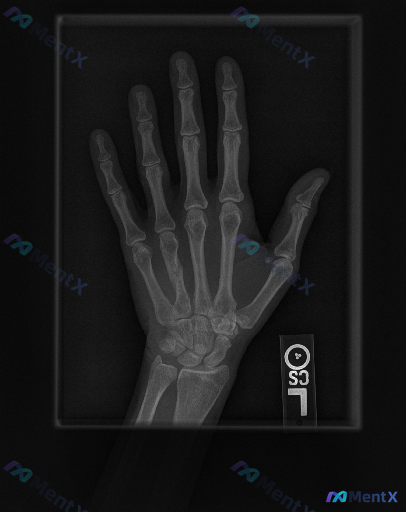

左手正位X光片报告看似无明显异常,但临床提示存在异常,你会优先关注哪一点?

整理到一份左手正位X光片的影像资料与临床背景:

影像表现概要

- 诸掌骨、指骨、腕骨骨皮质连续,未见明确骨折线、脱位或明显骨质破坏;

- 各关节间隙宽度大致正常,关节对位良好,未见明显退行性变;

- 拇指掌指关节尺侧可见一枚圆形边界清晰的高密度影,报告考虑为生理性籽骨;

- 软组织影轮廓尚自然,未见明显局限性肿胀或异物影;

- 骨骺线已闭合,符合成年人骨骼特征。

临床背景提示

临床确认该手存在异常。

想跟大家讨论一下:单看这份影像报告与临床背景的矛盾点,你会优先把目光放在哪里?这种“影像看似无大碍,但临床说有问题”的情况,你一般会怎么梳理方向?

📋答案:结合“临床-影像不匹配”的核心矛盾,现阶段更支持优先考虑**隐匿性创伤性病变**与**急性软组织损伤**,同时需关注拇指掌指关节尺侧高密度影的临床意义。